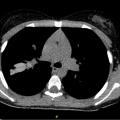

Place de l’imagerie dans le suivi de la mucoviscidose

La pathologie respiratoire au cours de la mucoviscidose représente encore l’essentiel de la morbidité et de la mortalité.1 La répétition des exacerbations respiratoires depuis l’enfance jusqu’à l’âge adulte accélère le déclin de la fonction respiratoire et favorise l’apparition de lésions radiologiques irréversibles telles que les…